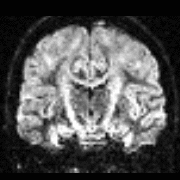

Quality Assessment

You should not trust any final outputs

WHY ?

DWI

FA

SSE

- One task - one QA

- General summary

- Global information

- Visual output

- Easy interface web-based